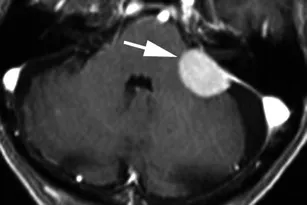

脑膜瘤MRI影像示例分析

案例三:83岁男性患者,头晕伴跌倒症状。增强轴位T1加权序列显示左侧桥小脑角区(箭头)均匀强化轴外肿块,宽硬脑膜附着伴硬脑膜尾,向前延伸至左侧内耳道,向后延伸至乙状窦。肿块覆盖左侧内耳道,无管内延伸。影像表现与病理结果符合脑膜瘤(WHO I级)。